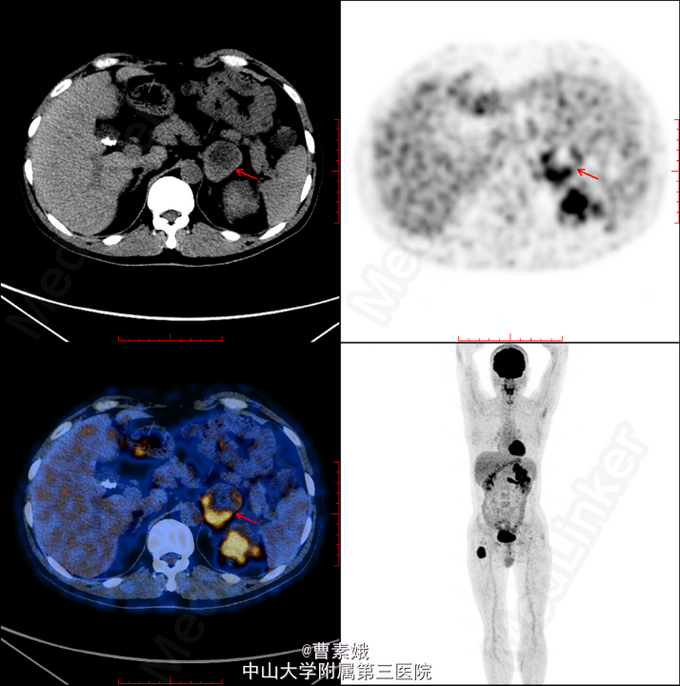

初步诊断:右股骨近端骨肿瘤(?)。 考虑右股骨肿物性质未明,遂于我院行全身PET/CT及腹部CT增强扫面,检查结果提示:1、左肾肿块并左肾静脉充盈缺损,代谢活跃,考虑左肾癌(透明细胞癌可能)并左肾静脉癌栓形成;双侧肾上腺座椅;腹膜后淋巴结转移;左侧股骨 经济股骨上段骨转移。随后患者行“左股骨肿物+左肾肿物穿刺活检术”,冰冻病理结果提示:左肾透明细胞癌,左股骨肿物考虑肾透明细胞癌转移。考虑患者肾透明细胞癌多发转移,无手术指征,转入肿瘤内科予索坦靶向治疗。